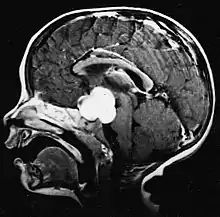

Pilocytic astrocytomas are often cystic, and, if solid, tend to be well-circumscribed. They are characteristically easily seen on computed tomography (CT scans) and magnetic resonance imaging (MRI).

Usually – depending on the interview of the patient and after a clinical exam which includes a neurological exam and an ophthalmological exam – a CT scan and/or an MRI scan will be performed. A special dye may be injected into a vein before these scans to provide contrast and make tumors easier to identify. The neoplasm will be clearly visible.

Visual aspect

Microscopically, an astrocytoma is a mass that looks well-circumscribed and has a large cyst. The neoplasm may also be solid.